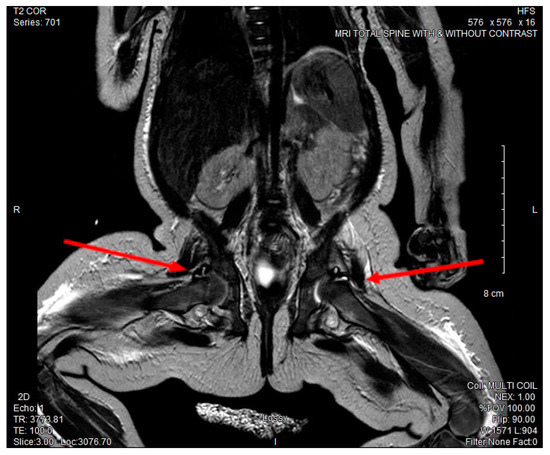

The patient required a packed red blood cell transfusion for a progressive normocytic anemia with hemoglobin nadir of 6.8 g/dL and a mean corpuscular volume of 76.9 fL on day 10 of illness. On the following day, the patient exhibited decreased movement of both lower extremities and severe discomfort with passive range of motion, but showed no erythema or swelling in any of her joints. With concern for extension of infection, CSF cytology was repeated and was consistent with interval improvement of her known meningitis [leukocyte count (WBC: 20/μL) with 15% segmented neutrophils, absent red blood cells (0/μL), elevated protein (131 mg/dL), and a normal glucose (39 mg/dL)]. MRI of her cervical, thoracic, lumbar spine, and hips showed increased fluid enhancement of bilateral hips and right elbow concerning for septic arthritis. (See Figure 2).

Figure 2. MRI full spine and hips with and without contrast. Abnormal T2 signal enhancement of bilateral hip joints.